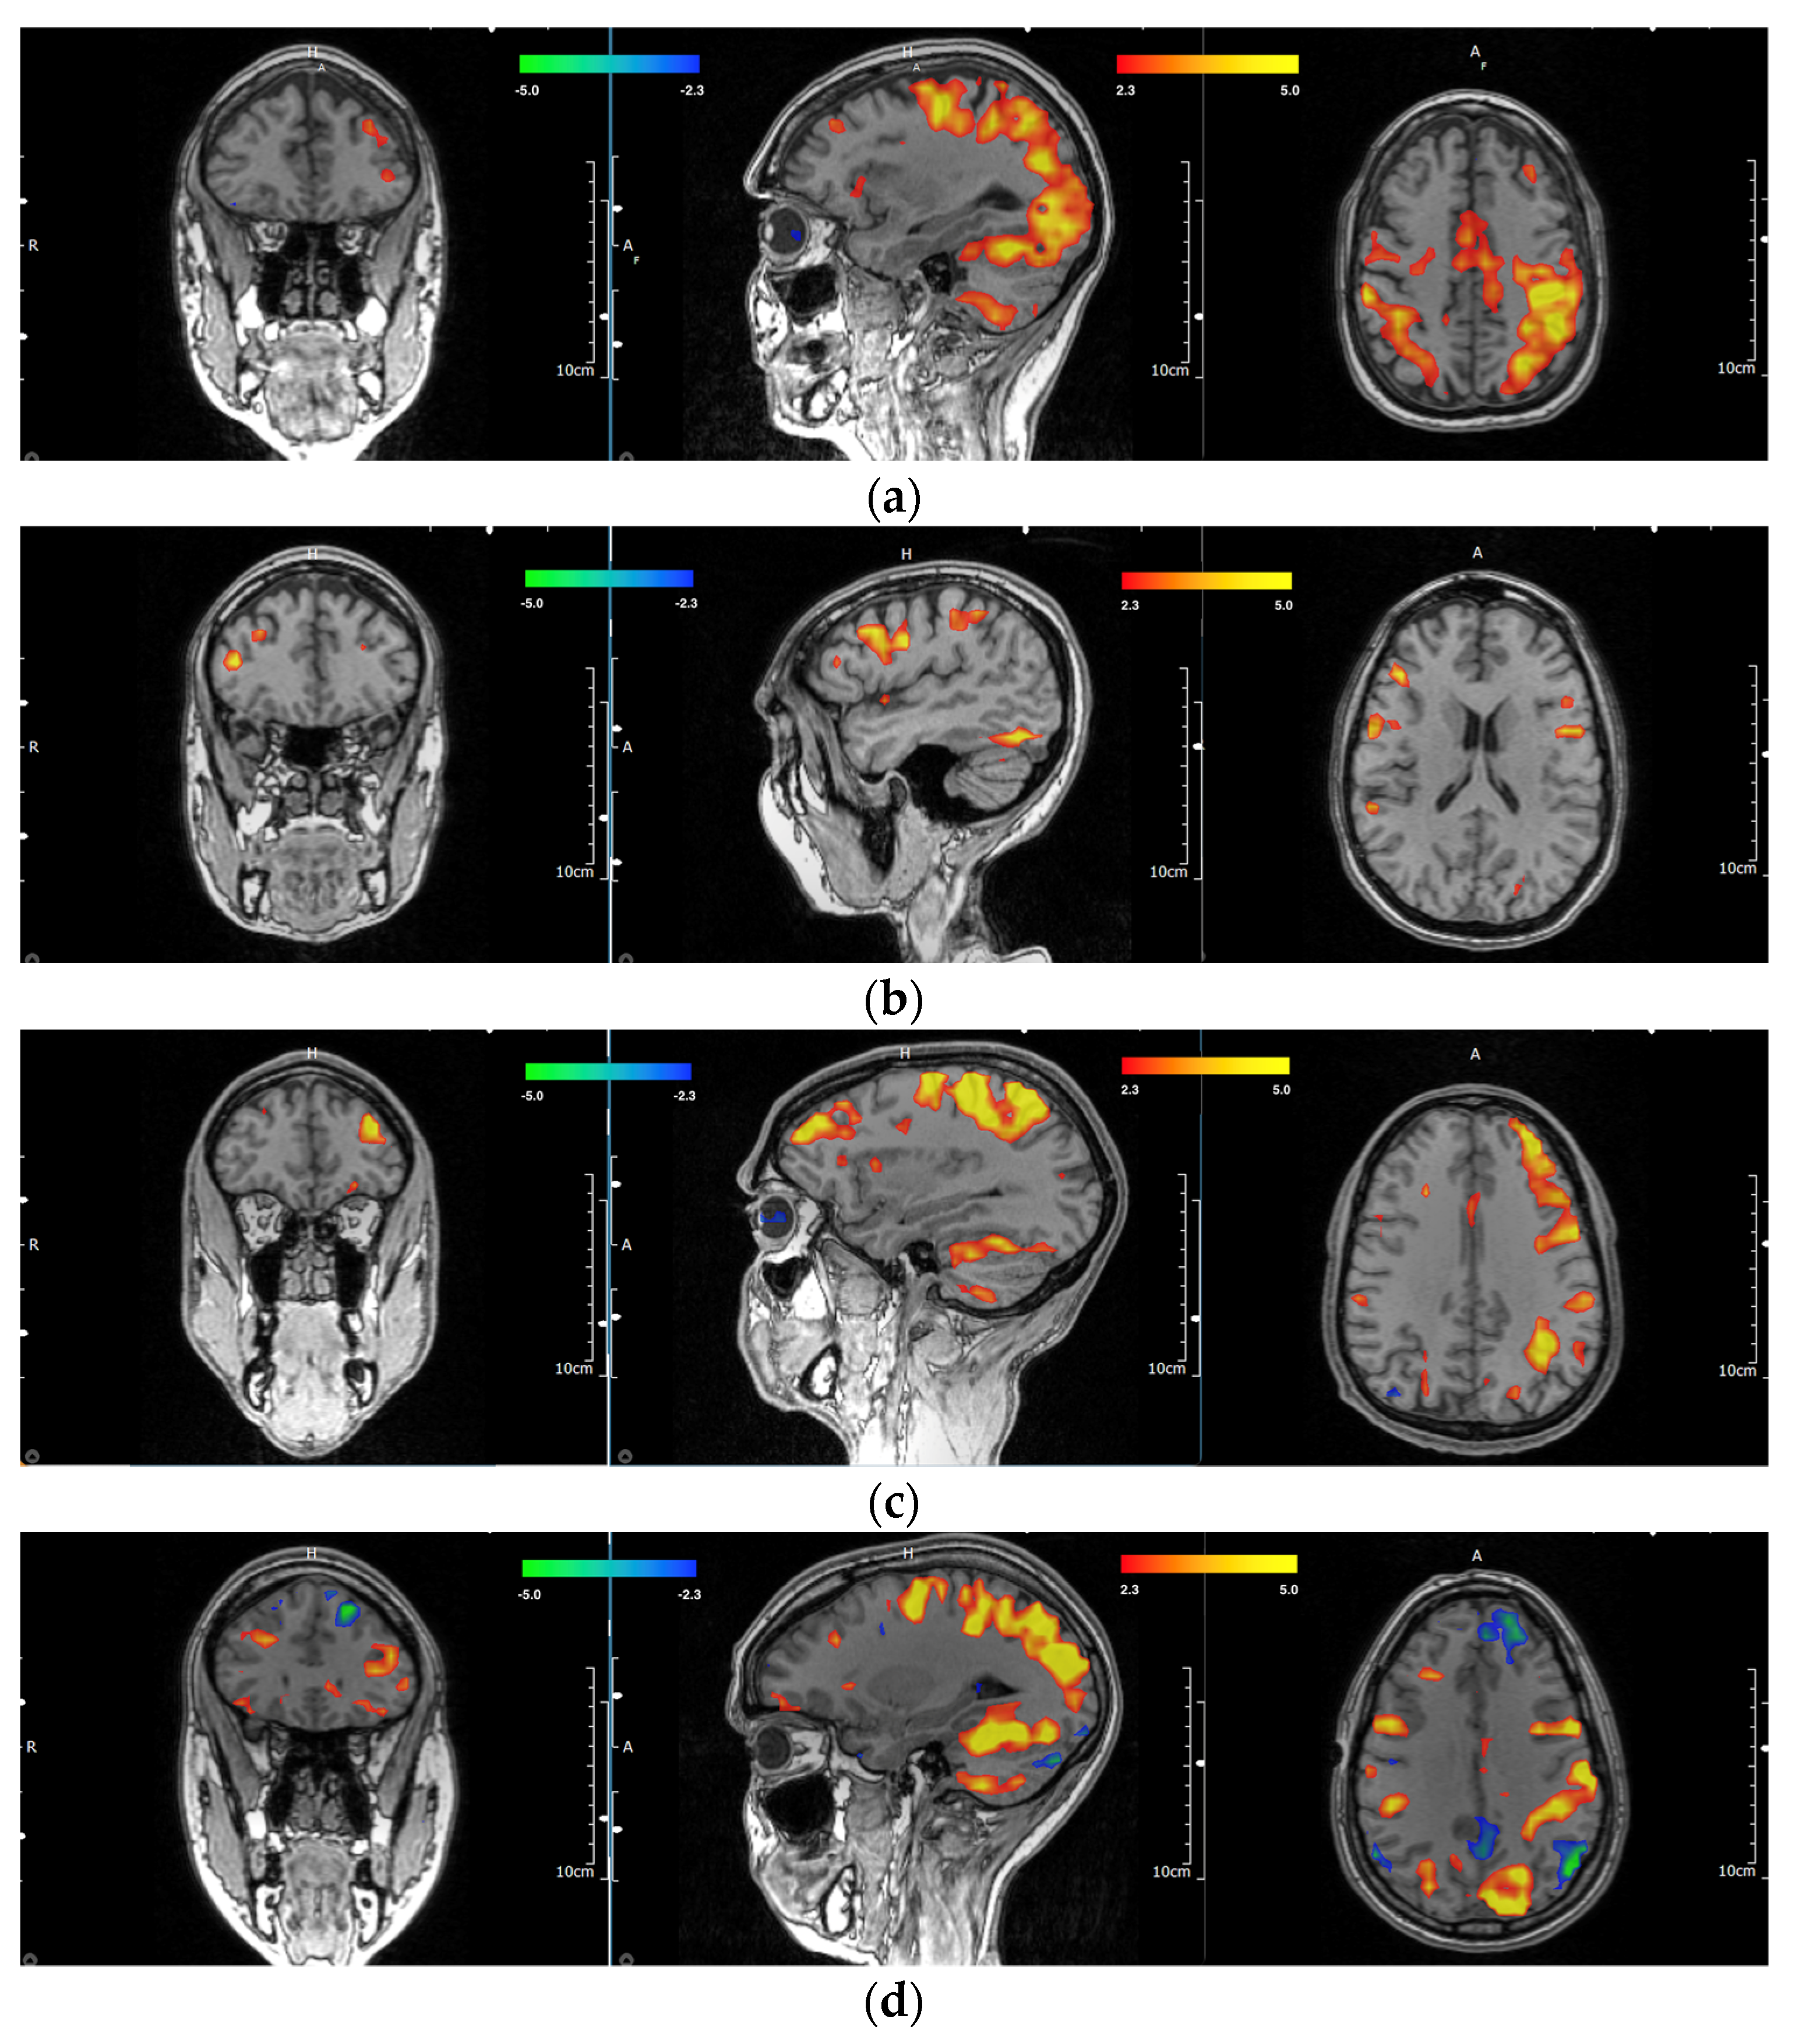

Out of the entire subset of 58 participants, there were a total of four ambidextrous participants, for which the investigators agreed on three of the scans for the primary dlPFC location. Of the ambidextrous participants, two (66.7%) were right hemisphere dominant, and one (33.3%) was left hemisphere dominant. Examples of multiple MRIs showing the handedness of individual participants with respective motor and dlPFC areas are shown in Figure 2a–f. A full breakdown of handedness and dlPFC lateralization can be found in Table 1. Full experimental details and results of all participants and their respective dlPFC scoring by blinded investigators can be found in Supplementary Table S1.

Figure 2. (af). Representations of different task-based handedness lateralization. (a). Coronal, sagittal, and axial sections of left-handed participant with left-sided dlPFC. (b). Coronal, sagittal, and axial sections of left-handed participant with right-sided dlPFC. (c). Coronal, sagittal, and axial sections of right-handed participant with left-sided dlPFC. (d). Coronal, sagittal, and axial sections of right-handed participant with right-sided dlPFC. (e). Coronal, sagittal, and axial sections of an ambidextrous participant with left-sided dlPFC. (f). Coronal, sagittal, and axial sections of an ambidextrous participant with right-sided dlPFC.